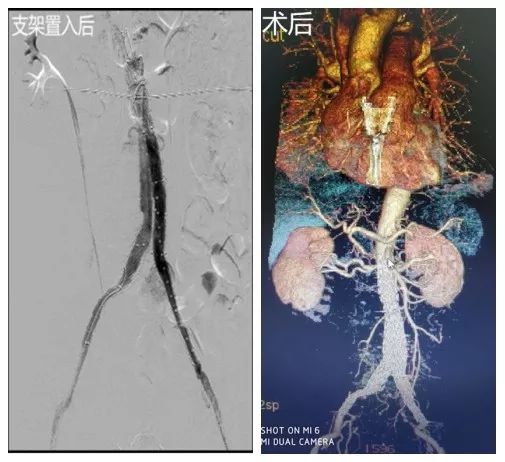

患者张某,69岁,腹痛5小时急诊入院,查体:心率120次/分,血压70/55mmHg贫血貌,腹部膨隆,腹肌紧张,全腹压痛,双下肢足背动脉搏动减弱,主动脉CTA提示:腹主动脉瘤右侧壁破裂并右侧腹膜后区-右肾周间隙血肿、骶前间隙积血,腹主动脉中下段-双侧髂总动脉动脉瘤并血栓形成。明确诊断后,立即送至我科,与家属交代病情取得理解后,麻醉、导管室、输血科、ICU等相关科室做好准备后,介入血管心脏外科李立涛副主任医师带领手术团队着手为该病人进行手术。克服患者血压低,左侧髂外动脉重度狭窄并短段闭塞,导管不能通过闭塞处的不利因素,李立涛副主任医师在团体的帮助下,依次予以覆膜支架隔绝破裂的腹主动脉瘤,放置1个支架主体及3个分支支架,造影见腹主动脉瘤被隔绝,未见显影,无内漏,双肾动脉及髂动脉显影良好,血流速度可,术后转ICU继续治疗,经过ICU悉心治疗后,术后1周复查主动脉CTA,动脉瘤隔绝良好,支架位置准确,患者康复出院。